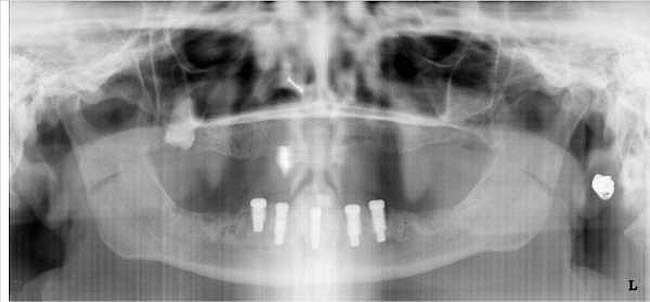

Figure 10a  Supra-eruption of the opposing arch, thus diminishing crown height space.

Figure 10a

Figure 10b  Supra-eruption of the opposing arch, thus diminishing crown height space.

Figure 10b

Figure 10c  Traditional fixed prosthodontics performed to level the opposing arch and regain sufficient crown height space.

Figure 10c

Figure 10d  Traditional fixed prosthodontics performed to level the opposing arch and regain sufficient crown height space.

Figure 10d